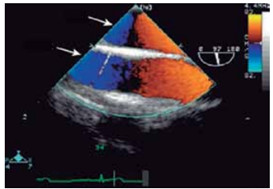

Ao realizar-se ecocardiograma transesofágico, nota-se a

imagem a seguir.

(GOLDSTEIN, S. A. et al. ASE’s Comprehensive Echocardiography. 2nd edition. Elsevier Health Sciences, 2016)

As setas superior e inferior indicam respectivamente: